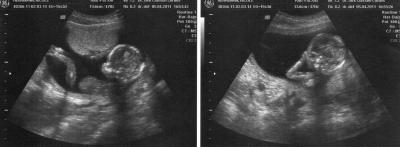

Hallo ihr Lieben, bin auch zurück von der VU und alles ist in bester Ordnung . Baby ist ca. 20 cm gross und 130 gr schwer/leicht . Herzchen hat kräftig geschlagen und wir durften einen ausgiebigen Blick zwischen die Beinchen werfen uuund was sahen wir? Einen kleinen Pippimann !!! Mein FA ist sich zu 100 % sicher und hat es sogar schon in meinen Mutterpass eingetragen. Mein Freund und mein Söhnchen waren auch dabei und haben sich na klar riesig gefreut über den männlichen Zuwachs in der Runde Hänge noch 2 Bildchen an ;-) LG Nici

Auf dem linken Bild ist es ja wirklich eindeutig :o).Toll, dass dein Bauchbewohner so zeigefreudig war. Herzlichen Glückwunsch zum Sohnemann! Liebe Grüße Eolair

na das ja mal ein beweisfoto...-herzlichen glückwunsch zum sohnemann! und euer knirpsi ist auch schon ganz schön groß... Lg